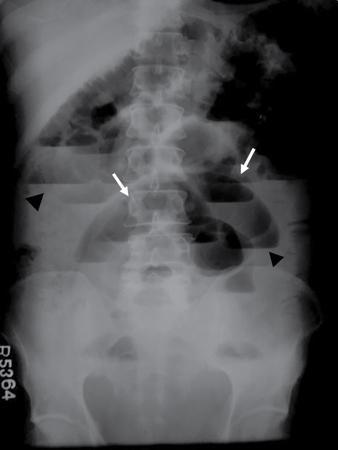

UNDERSTANDING THE ADULT ABDOMINAL RADIOGRAPH: TECHNIQUES AND INTERPRETATION Tanvi Modi Radiography of the abdomen is a common practice for the evaluation of abdominal organs. The anatomy and pathology of digestive, hepatobiliary and genitourinary systems can be assessed using radiographs, either as a stand-alone practice or as a primary imaging modality followed by contrast studies, ultrasound or cross-sectional imaging. In addition, abnormalities of the musculoskeletal or integumentary system can also be deduced on the basis of abdominal radiographs. This chapter intends to give an overview on the techniques and positioning in abdominal radiography as well as interpretation of normal and abnormal features. While superior imaging modalities such as ultrasound, computed tomography (CT), magnetic resonance imaging, capsule endoscopy and the likes have taken over abdominal imaging by and large, radiography still holds a pivotal role in certain situations and conditions, such as: The standard abdominal radiograph is taken in supine position and anteroposterior projection. This is also popularly known as the KUB (kidneys-ureters-bladder) radiograph. Previously, supine as well as erect radiographs were performed in all patients; however, this is not commonly done due to high-radiation dose. For all indications of abdominal radiography, including acute abdomen, supine radiographs are sufficient in terms of radiographic diagnosis, with the exception of perforation for which an erect chest or lateral decubitus radiograph can be performed if there is clinical suspicion. Patient should lie supine on the imaging table with median sagittal plane at right angles to the table and coincident with the midline of the table (Fig. 7.1.1.1). The body is divided into equal right and left halves by the median sagittal which passes through the sagittal suture of the skull. Pelvis should be adjusted so that the anterior superior iliac spines are equidistant from the table top. Gonadal shields, in the case of male patients, should be placed with the upper edge of the shield at the level of pubic symphysis. Although rarely used for female patients, these should be positioned between the anterior superior iliac spines and the pubic symphysis. The centre point of the image receptor should be approximately located at a point 1 cm below the line joining the iliac crests. The X-ray beam should be in a vertical direction, perpendicular to the table top and image receptor at the centre point. Collimation should be such that the soft tissue and subcutaneous region along lateral aspects of the abdominal cavity should be covered within the image. Also, the superior extent involving diaphragm and inferior extent involving the inferior pubic rami is important to look for any lower chest pathologies or any inguinal hernia. 35 × 43 cm (14 × 17 inches) in portrait orientation. On an average, abdominal radiograph exposes a patient to a dose of approximately 1.5 mSv, which is equivalent to 75 chest radiographs or 1/6th dose of a standard CT of the abdomen. The entrance skin dose is approximated to be 4 mGy. At such an effective dose, the additional lifetime risk of fatal cancer is 1 in 30,000. The exposure time is kept short. Patient is asked to exhale completely and hold their breath, with exposure taken at this point of full expiration to ensure imaging of abdominal organs in their natural positions. Modifications of this technique can be made depending on patient habitus and clinical condition. Kilovoltage peak (kVp) should be set to allow adequate visualization of abdominal soft tissue structures as well as semiopaque renal and biliary calculi. Average kVp is set at 70–85 kV. 102 cm (40 inches) Grids are commonly used to reduce scatter radiation. Placement of side marker on the image receptor at the time of radiographic exposure is essential. Bowel pattern depiction should be such that there is minimal lack of sharpness. Standard guidelines for abdominal radiography dictate that the radiograph should extend from the diaphragm up to the level of inferior pubic rami and must include the lateral abdominal wall musculature. The abdomen is divided into four quadrants on the basis of two perpendicular lines (Fig. 7.1.1.7). The vertical line passes through the mid sagittal plane and crosses the umbilicus and symphysis pubis. The horizontal line is a transverse line across the umbilicus at 90 degrees to the vertical line and is situated at the level of L4–L5 intervertebral disc. The quadrants are as follows: Another division system is dividing the abdominopelvic cavity into nine regions using two vertical and two horizontal planes (Fig. 7.1.1.8). The vertical planes, also known as the right and left lateral planes, are parallel to the midsagittal plane between midline and anterosuperior iliac spines on either side. Of the two horizontal planes, the upper transpyloric plane is at the level of lower border of L1 and the lower transtubercular plane is at the level of L5. The nine regions are: On a standard radiograph, the exposure should be such that the stomach, bowel loops, outlines of liver, spleen, kidneys, psoas muscles should be well identified. Also, lumbar transverse processes should be seen. Arch of the pubic symphysis should be visible to evaluate bladder region. A well-centred film without rotation will demonstrate bilaterally symmetrical lower ribs, iliac wings, ischial spines and obturator foramina. Different structures seen on an abdominal radiograph can be classified into five basic densities: Identification of different structures depends on the relative degree of contrast between their densities. The demarcation is clearer in chest and is diminished in abdomen due to relative similar soft tissue density of various structures. On a normal radiograph, relatively large amounts of gas in stomach and colon with minimal small bowel gas can be seen. Further, colonic gas can vary from negligible to extensive, mimicking obstruction pattern; however, usually the gas is enough to delineate colonic haustral pattern. Faecal matter gives a mottled appearance to colonic gas. Short-air fluid levels on an erect radiograph may be seen even in normal cases. The normal appearance of small bowel loops on an abdominal radiograph follows the rule of threes: Stomach is seen in the left upper quadrant and is visualized when distended with air. It is commonly seen extending from T11 to L2 level. Common feature identifying the stomach is the fundal gas which is usually seen as an air fluid level within the gastric lumen. Small bowel loops are distributed to the centre of the abdominal cavity and large bowel loops are peripheral. Duodenum is predominantly situated in right upper quadrant. It extends to left upper quadrant in the region of duodenojejunal flexure. Jejunum occupies the left upper and lower quadrants and is easily identified due to the presence of thick, numerous, closely spaced valvulae conniventes (Fig. 7.1.1.9A). The ileum occupies both lower quadrants and extends into right upper quadrant. Ileum has few and less prominent valvulae as compared to jejunum (Fig. 7.1.1.9B). Ascending and descending colon are retroperitoneal and have relatively fixed positions along lateral aspect of the abdominal cavity on either side. Transverse and sigmoid colon, on the other hand, may have a variable position due to their mobility along mesocolon and redundant pattern. These can be identified with confidence on account of haustrations and faecal matter (Fig. 7.1.1.10). Haustrations are usually well seen in ascending and transverse colon and poorly delineated beyond splenic flexure. Caecum is in the right lower quadrant, though it may be mobile or pulled up. Rectal gas is usually seen in the midline at the level of pelvis and its presence rules out large bowel obstruction. All these positions may vary due to anatomical conditions such as malrotation or pathological conditions, for example volvulus. Liver, spleen and renal outlines cannot be completely traced with precision due to the overlap by bowel loops. On a frontal projection, the liver appears as a triangular structure occupying right and left hypochondrium and epigastric region. Occasionally, the right lobe may be seen extending lower than the right renal shadow. This is a normal variant known as Reidel’s lobe. Gall bladder is situated in the posterior and inferior region of the liver and any pathology of the gall bladder should be looked for in this region. On a lateral radiograph, the gall bladder is anterior to the midcoronal plane. This helps in distinguishing gall bladder calculi from renal calculi, which will be more posteriorly situated. Spleen is seen in left upper quadrant/left hypochondrium, flushed to left lower ribs and left hemidiaphragm. Pancreas is present in the epigastric region (right and left upper quadrants) and is usually not identified in the absence of a pathology. The kidneys are bean-shaped retroperitoneal organs which are seen on either side of the vertebral column and lateral to psoas muscles. Due to the presence of liver on the right side, this kidney is slightly lower in position as compared to its contralateral counterpart. The visualization of kidneys on radiographs is facilitated by the surrounding fatty capsule. Kidneys lie between T11–12 and L2 level, with left kidney 1 cm higher than the right. Psoas muscle shadow can be normally seen along lateral aspect of lumbar spine bilaterally and is mildly concave (Fig. 7.1.1.11). Abdominal wall muscles are not routinely assessed on radiography; however, inclusion of lateral abdominal wall (muscles as well as subcutaneous plane) is a must while performing radiography. The flank stripe or the properitoneal fat stripe is a fat density linear concavity seen along lateral abdominal wall (Fig. 7.1.1.11). It is bound by the paracolic gutters and air-filled ascending and descending colon. All the solid organs in the abdomen are identified due to the fat density outlining them. Distortion of these fat lines helps in identifying organomegaly or focal mass lesions. The dome of urinary bladder is outlined by fat, which aids in differentiating its density from other soft tissue structures of the pelvis. Not all calcifications seen on abdominal radiograph are abnormal. Some may depict age-related changes such as vascular calcifications involving abdominal aorta, pelvic vessels, splenic artery in the region of left upper quadrant. Within the pelvis, phleboliths may be seen and mistaken for urinary calculi. Assessment of lumbosacral spine, iliac bones and femoral heads can be made on the basis of plain radiography. Degenerative changes may be commonly seen. Lower ribs can also be evaluated for pathologies. Dilated small bowel loops with rounded soft tissue density in midline over umbilical region suggests obstruction secondary to umbilical hernia. Pneumoperitoneum must be looked for in all cases of acute abdomen. While erect chest and left lateral decubitus radiographs can detect even 1 mL of free air, there are multiple signs on supine radiograph to suggest this diagnosis, for example Rigler’s sign, falciform ligament sign, football sign (Figs. 7.1.1.24 and 7.1.1.25). Retroperitoneal perforation may demonstrate air outlining psoas muscles and retroperitoneal organs. Small amount of free air may persist in the abdominal cavity up to 3 weeks after surgery, although it usually resolves within a week. Clinical history is important in such cases. Air foci within the bowel wall may represent bowel ischaemia/strangulation. Linear gas patterns in right hypochondrium may be due to two causes, that is pneumobilia and pneumoporta. The former can be seen normally postbiliary surgery, sphincterotomy, ERCP or in the case of abnormal fistulous communication between bowel and biliary tree (Fig. 7.1.1.26A). Pneumoporta (Fig. 7.1.1.26B) is a red flag and warrants further investigation to look for conditions such as mesenteric ischaemia and toxic megacolon. Pneumobilia is more centrally located whereas air shadows in pneumoporta are seen reaching up to periphery of liver. Air foci over renal shadows (Fig. 7.1.1.27), gall bladder or pancreas, in the absence of recent procedural history, suggest fulminant infection and mandate urgent intervention. Central midline calcific foci between T9 and T12 vertebrae can be attributed to calcific pancreatitis (Fig. 7.1.1.28). In the left upper quadrant, areas of calcification seen involving a shrunken spleen may be seen in autosplenectomy. In right upper quadrant, calcified gall stones may be seen. These tend to be small, multiple, uniformly circumscribed and ring-like in appearance with central translucency (Fig. 7.1.1.29A). Mercedes Benz sign, a triradiate pattern of gas lucency, is associated with gallstones. In contrast, renal calculi are more commonly solitary, irregular, of homogenous density, conform to renal calyceal or pelvic outline (Fig. 7.1.1.29B) and are sometimes of staghorn configuration. On lateral view, the gall stones are more anteriorly located as compared to renal calculi, which may be partly superimposed on lumbar vertebrae. Ureteric calculi tend to overlap bony structures such as lumbar transverse processes (Fig. 7.1.1.29B) or sacroiliac joints. Extensive or patchy, curvilinear calcification of gall bladder wall is known as porcelain gall bladder which is often associated with malignant transformation. Calcification involving adrenal glands may be secondary to infection or haematoma, or a congenital condition known as Wolman’s disease where there is bilateral involvement. Discontinuous discrete midline tram track calcification in the abdomen may indicate atherosclerotic changes in abdominal aorta and branch vessels. However, when the calcification is in a globular pattern and seen below the level of L2 vertebra, aortic aneurysm should be suspected (Fig. 7.1.1.30). Appendicoliths, though not commonly seen, may sometimes be detected in right iliac region. Pelvic calcifications: vesical calculi, distal ureteric or vesicoureteric junction calculi, calcified fibroids, ovarian dermoid with tooth-like calcifications (Fig. 7.1.1.31) may be the cause of abdominal pain and should be diligently looked for. Vesical calculi are usually more large and central in location whereas calcification due to fibroids may be more lateral. Schistosomiasis is another cause of bladder wall calcification, as is calcification of bladder tumours. Phleboliths tend to be bilaterally symmetrical, with a lucent centre unlike ureteric calculi. While it is believed that phleboliths are located below the level of ischial spines and ureteric calculi above, this is not always true and should be confirmed with CT. Fluid may collect adjacent to properitoneal fat line, forming a linear soft tissue density separating the fat line from the ascending or descending colon. Hellmer’s sign demonstrates medial displacement of lateral edge of liver (hepatic angle), due to fluid collection or ascites. Gross ascites may appear as generalized abdominal haziness or diffuse increased density of pelvis. Abscesses can involve any solid organ and in such cases may be difficult to demonstrate on plain radiography alone. Enlargement of organ or faint gas densities within can be suggestive of the same. In the case of peritoneal abscess, mottled density due to air, fluid and necrotic contents point towards this diagnosis, especially in right iliac fossa in association with appendicitis. Retroperitoneal abscess, similar to any retroperitoneal mass, may cause displacement of retroperitoneal structures (Fig. 7.1.1.32). Subdiaphragmatic abscesses may show concomitant ipsilateral pleural effusion (Fig. 7.1.1.33). These should be differentiated from Chilaiditi syndrome. Fluid and soft tissue lesions present with the same density on radiographs. While it is difficult to characterize the lesion and organ of origin, clues for the same can be provided by organomegaly (Fig. 7.1.1.34), distortion of fat surrounding solid organs, displacement of bowel loops or solid organs. For example, a retroperitoneal lesion may cause anterior or inferior displacement of kidney, a pelvic mass may cause upward displacement of small bowel loops. Different densities such as fat or calcification may help in identifying organ of origin (e.g. fat and tooth densities seen in ovarian dermoid). Convexity of margins of psoas muscle on an abdominal radiograph can be due to haematoma, abscess or intramuscular tumour. Radiographs are performed for the initial diagnosis of foreign body in the abdomen including type, number of foreign bodies, location, size and shape (Fig. 7.1.1.35). Radiolucent foreign bodies such as wood, plastic, chicken bones will not be easily identified on radiography. Low kVp (65–70 kVp) can increase contrast and help identify these objects. In addition to an abdominal radiograph, chest radiography is also performed to exclude aspiration or oesophageal location of foreign body. Ingested or introduced foreign bodies may cause complications such as obstruction, perforation, fistula formation and sepsis. Hence, once their presence is confirmed, follow up radiography must be performed until they are eliminated. One must look for fractures/dislocation injuries involving the vertebrae or pelvic bones, especially after history of trauma. Lucent expansile lesions or sclerotic bony deposits which represent neoplasms, absent pedicle sign in cases of metastasis, metabolic bony changes such as rugger jersey appearance, Paget’s disease, arthropathies such as ankylosing spondylitis with bamboo spine appearance and sacroiliitis (Fig. 7.1.1.36) are some of the conditions which may be diagnosed based on an abdominal radiograph. Overlap of bowel loops over iliac blades may lead to a misdiagnosis of lucent lesions and should be evaluated with caution. Basal pneumonia may be the cause of acute abdominal pain and should be looked for in abdominal radiography. Similarly, pleural effusion, pericardial effusion, calcified pleural plaques, achalasia, interstitial fibrosis are few other findings that can be seen in lower chest on an abdominal radiograph. Basilar atelectasis can give a deceptive appearance of pneumoperitoneum (Fig. 7.1.1.37). Surgical clips, commonly in right hypochondrium after cholecystectomy, drainage tubes, ventriculoperitoneal shunts, femoral line catheters, IVC filters, stents (vascular, renal, biliary) (Fig. 7.1.1.38), stoma bags, contraceptive devices are some structures that may be seen in an abdominal radiograph. Correct knowledge of patient history and normal locations of these structures prevents misdiagnosis. Certain artefacts may be projected upon the radiograph due to surface structures such as trouser buttons, body piercing, sequins over clothing and should not be considered as a pathology. Multiple skin surface nodules in cases of neurofibromatosis, soft tissue focal swellings, such as abscesses, lipomas, haematomas, desmoid tumours and malignant lesions may be incidentally seen on radiography. These can be further evaluated using ultrasound or CT. Subcutaneous emphysema is another finding that may be seen in lower abdominal wall secondary to retroperitoneal perforation or diffusely along abdominal wall in the case of bowel perforation (Fig. 7.1.1.39). Foreign bodies such as bullets and pins may be seen lodged in abdominal wall. A systematic approach to abdominal radiographs is important for accurate diagnosis as follows: Despite the development of newer techniques for imaging of the abdomen, plain radiography still holds an important place in the initial assessment of acute abdomen. Positive and negative findings on an abdominal radiograph can direct further investigation. Ideal positioning, recognition of normal appearances and keen scrutiny for pathologies is a sine qua non for radiologists reading a plain film of the abdomen. OESOPHAGOGRAM Padma V. Badhe, Vikram Reddy, Sultan Moinuddin Shaukatali, Zillani Alam, Ravi Varma, Abhishek Bairy, Dasari Ravikiran, Revati Tekwani, Soniya Patankar, Megha Nair, Gautham Shankar Oesophagogram is the process of obtaining radiological images and simultaneous motion recording to evaluate function and disorders of pharynx, oesophagus and proximal stomach. Oesophagogram is usually done primarily to evaluate dysphagia. Some of the common indications are oesophageal motility disorders, strictures, gastro-oesophageal reflux disease (GERD) and suspected masses. It can also be used to detect uncommon anomalies like vascular rings/slings and aberrant anatomy. It also helps to evaluate further in cases where there is inability to pass upper GI scope. Double-contrast oesophagogram is mainly indicated in early mucosal disease like erosion, polyp, infection and tumours. If a motility disorder is suspected, dynamic technique (e.g. videofluoroscopy) is used for dysphagia or aspirations in cases of stroke, neuromuscular disorders, post head and neck surgery or radiation. Barium oesophagogram is contraindicated in suspected cases of perforation and tracheoesophageal fistula, aspiration, rarely if there is hypersensitivity to barium suspensions. It is also contraindicated in suspected oesophageal perforation where a water-soluble contrast agent is more suitable. However, ionic water-soluble contrast agent is better avoided in cases of aspiration or fistula with airway. The contrast examination of the pharynx is dangerous in cases of acute epiglottitis and must be ruled out on plain radiograph. An 80% w/v barium suspension is used in full column views. However, 200%–250% w/v barium suspensions is usually required for mucosal relief films. The barium sulphate mixture is fed to the patient either by spoon, by glass, or through a drinking straw, depending on its consistency. In videofluoroscopy, the pharyngeal phase of swallowing is usually safer with barium pudding than with thick barium and safer with thick barium than with thin barium. However, if the major abnormality is poor pharyngeal contraction leading to stasis in the piriform sinus (and epiglottic tilt is normal), a thin liquid is safer. Epiglottic motility is better assessed with thin barium because thick barium often obscures the epiglottic tip. Fluoroscopic equipment capable of cine fluoroscopy and capability for rapid sequence spot images (high frame rate) is needed for this examination, Barium suspension, straw, glass, Lead apron and radiation protective equipment. The patients are instructed to fast after midnight before the day of the examination. The pharynx should be made as dry as possible during the examination as high-density barium adheres to dry pharyngeal mucosa. Activities like smoking, chewing gum and lozenges must be abstained before the procedure as they impair barium coating by increasing the salivary secretion. Regular oral medications must be taken with sips of water; however, insulin must be skipped on the morning of examination. The major principles of a good oesophagogram includes mucosal coating, distension and projection. A routine oesophagogram consists of screening of the oral, pharyngeal and oesophageal phases of swallowing, single and double-contrast examination of pharynx, single contrast, double-contrast and mucosal relief views of the oesophagus. In cases of dysphagia, the examination is tailored depending on whether the symptoms are either pharyngeal or oesophageal and initial fluoroscopic findings. If patients’ symptoms are suggestive of oral or pharyngeal disorder then pharynx is evaluated first. Similarly, if patient is suspected to have thoracic oesophageal disease then, double-contrast examination of the oesophagus is performed before the pharyngeal evaluation. During an oesophagogram the positioning of the patient varies according to the type of examination (Table 7.1.2.1).